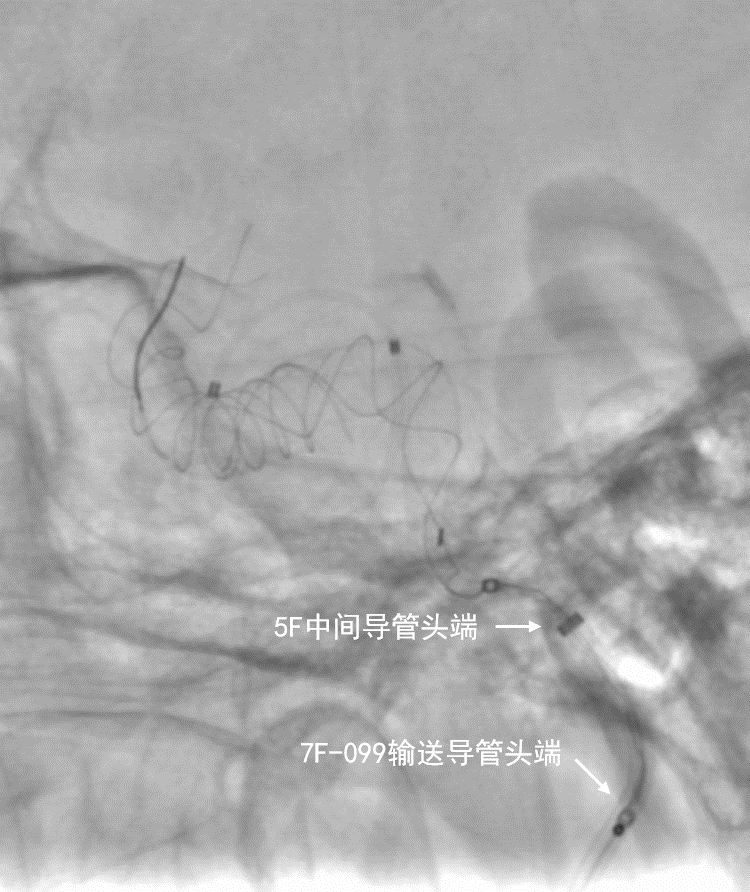

动脉长鞘怎么置入深谋远路 | 千人皆翘首,万唤今始来——国内首款7F长鞘在血流导向密网支架联合弹簧圈栓塞治疗动脉瘤的首次应用_https://www.jmylbn.com_新闻资讯_第29张

动脉长鞘怎么置入深谋远路 | 千人皆翘首,万唤今始来——国内首款7F长鞘在血流导向密网支架联合弹簧圈栓塞治疗动脉瘤的首次应用_https://www.jmylbn.com_新闻资讯_第30张

深瑞达7F输送导管,中间导管和弹簧圈微导管的位置关系